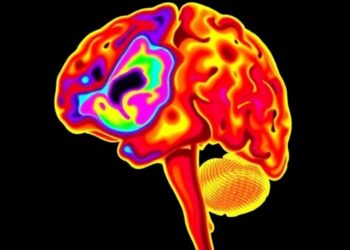

Cerebral NIRS: Key in Managing Post-Hemorrhagic Dilation?

In recent years, the quest to improve neurological outcomes in neonates affected by severe brain injuries has intensified, bringing cutting-edge...